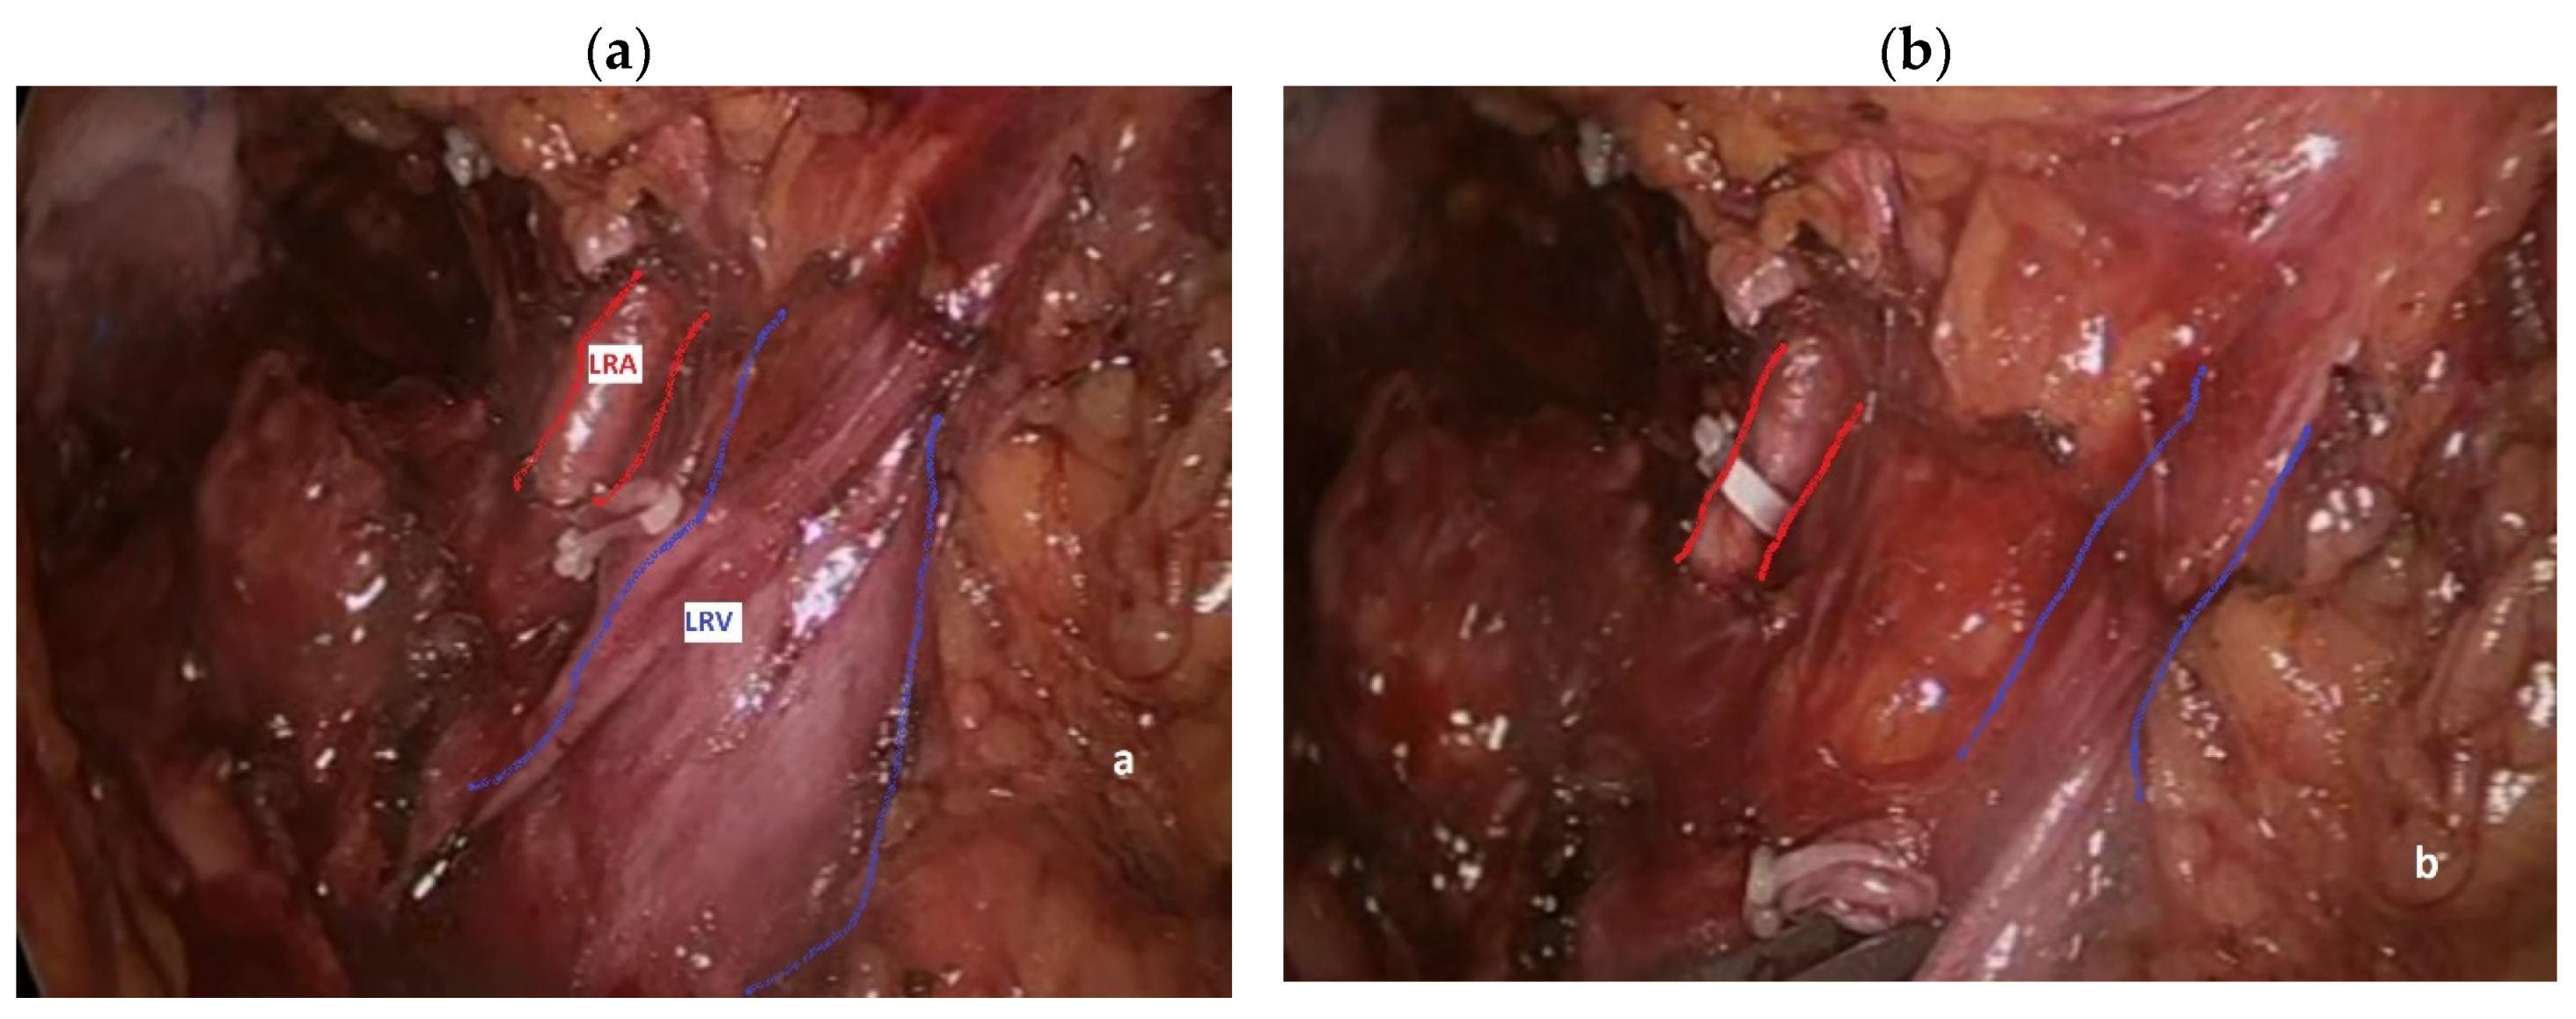

During left nephrectomy, the perceptive deficit manifests itself in a completely similar way: the surgeon determines a lesion of the SMA and/or the CT convinced that he is instead dealing with one or more LRA [15,30]. Actually, during transabdominal left nephrectomy, either open or mininvasive, the surgeon generally takes down the splenic flexure of the colon and directly dissects the renal hilum, finding the LRV first and the LRA immediately after (Figure 4a), lying behind it in 90% of cases [12]. Thereafter, an occluding clip is generally placed on the LRA first (Figure 4b), followed by clipping and division of the left renal vein, in order to avoid renal venous engorgement.

Figure 4. Dissection of the left renal hilum during left nephrectomy: a) LRA (red lines) lies posteriorly to a blood-filled LRV (blue lines); b) once the LRA (red lines) is clipped, the LRV (blue lines) appears emptied.